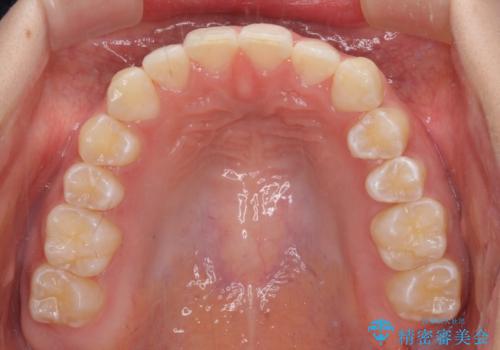

- 前歯の叢生と、奥歯の咬み合わせの悪さを気にして来院された患者様です。

左下には後続永久歯の欠損した乳歯が残存しており、叢生を相まって咬合関係が乱れていました。

乳歯は抜歯し、インビザラインにて矯正治療を行いながら、並行してインプラントによる補綴治療を行うこととしました。

矯正治療が終わるタイミングに合わせてインプラントの埋入を行っていたので、矯正治療を終了すると同時にセラミック補綴治療を行えました。

短期間でしっかりと治療を終えることができました。